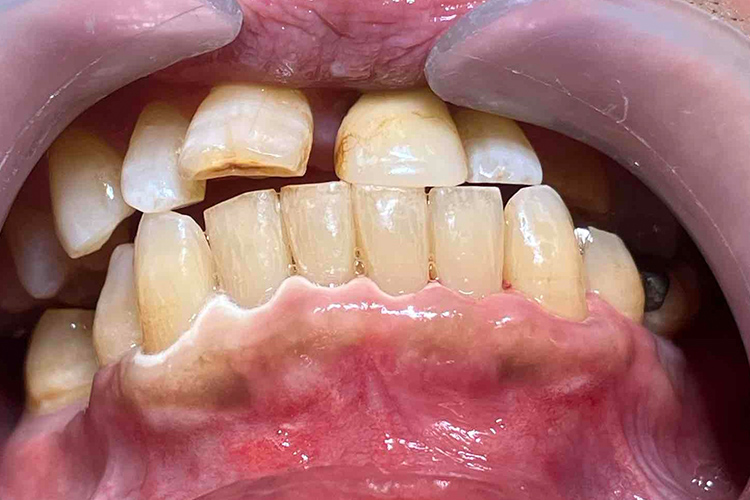

実施例②

この患者様は、スケーリングより歯周ポケットが6mm以上ある患者様で、ご本人も歯周病になりかけている自覚がありました。また、口臭も気になされていましたので、ブルーラジカルの適用症例と判断し、施術を行いました。

実施前

施術前のレントゲンと口腔内写真です。